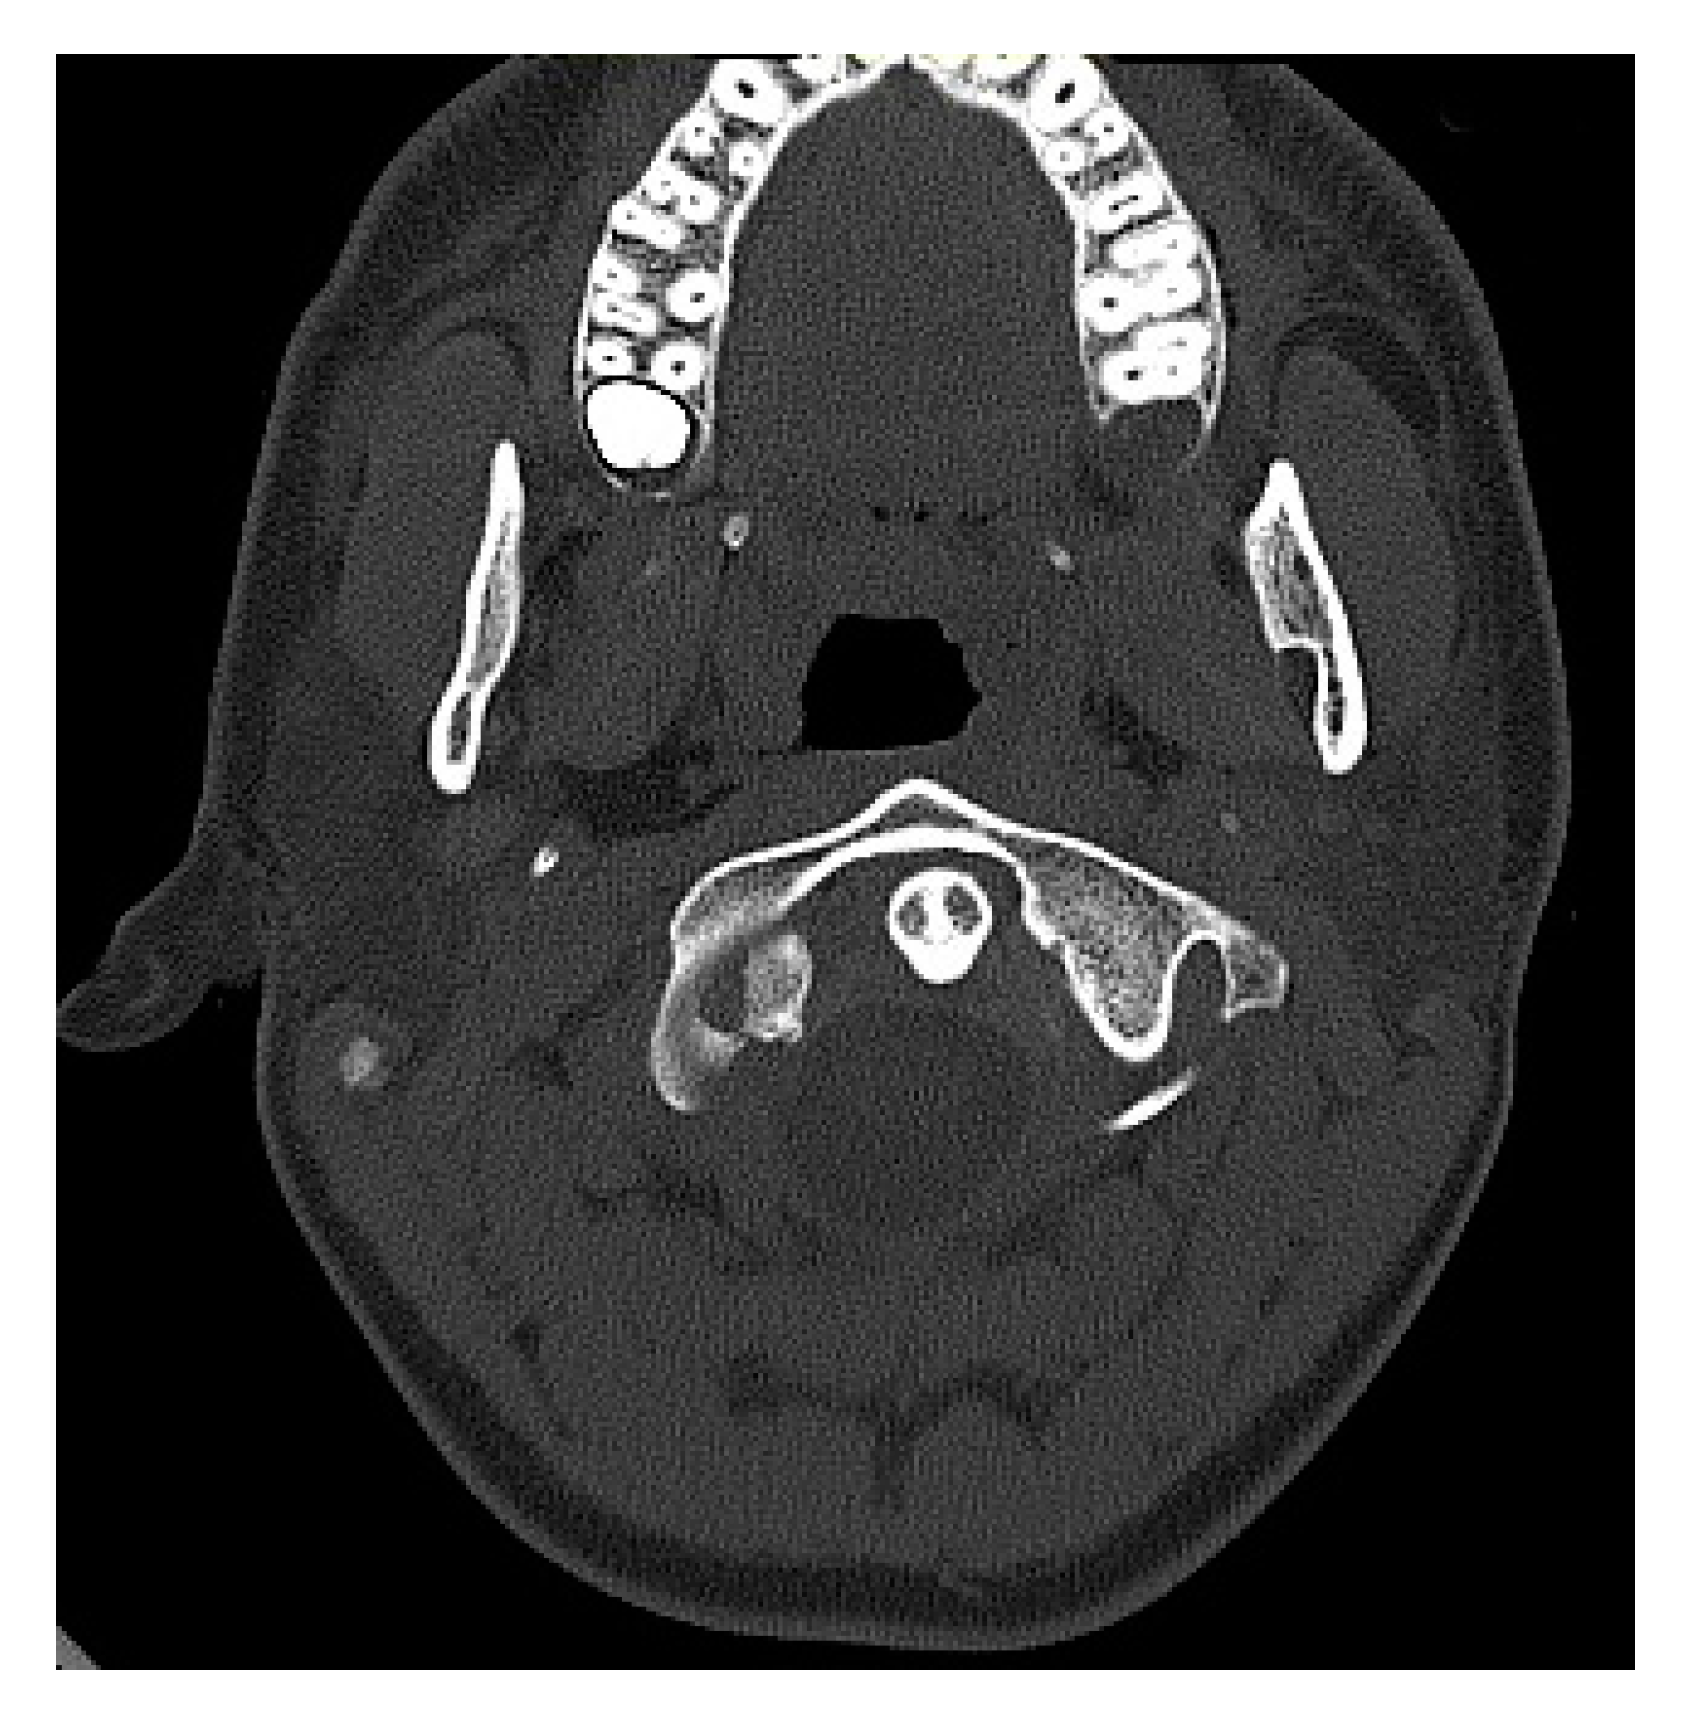

| Name (Initials) | Sex (Male/ Female) | Age (Years) | Anderson Montesano Classification | Tuli Classification | Cause of Injury | Accompanying Injuries | Immobilization Method |

|---|---|---|---|---|---|---|---|

| P.P. | M | 15.2 | III (unstable) | IIB | Road traffic accident (car passenger) | Fracture frontal bone, fracture frontal sinus, contusion of frontal lobe | Halo-vest immobilization: 12.5 weeks |

| K.D. | F | 15 | III (unstable) | IIB | Pedestrian hit by car | Lung contusion, brain concussion, multiple abrasions | Halo-vest immobilization: 13 weeks |

| R.M. | F | 18 | I (unstable) | IIB | Road traffic accident (car passenger) | Pneumothorax, neurogenic vocal cord injury, post-traumatic aphasia | Halo-vest immobilization: 14 weeks |

| S.D. | M | 14.7 | III (stable) | IIA | Road traffic accident (car passenger) | Fracture of frontal bone, fracture of nasal bone, subdural hematoma | Minerva-brace immobilization |

| B.W. | F | 16 | I (stable) | IIA | Fall from a height | Fracture of frontal bone, fracture of nasal bone, subarachnoid hemorrhage, fracture of transverse process Th3-5, fracture of radius | Minerva-brace immobilization |

| M.O. | M | 16.1 | I (stable) | IIA | Bicycle incident | Fracture frontal bone, fracture maxillary sinus, fracture orbit, metacarpal fracture | Minerva-brace immobilization |